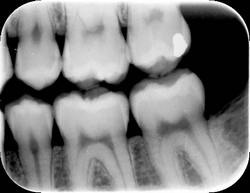

However, the human eye is only capable of distinguishing 32 shades of gray, which corresponds to a spatial frequency ranging from 5 to 7 lp/mm without magnification. The question then becomes, does the magnitude of a digital system spatial resolution above about 10 lp/mm make any diagnostic difference in the clinician’s ability to recognize pathosis radiographically? The answer is still being debated, but at least from our viewpoint, which can be supported from some of our initial investigations into this question, 1,2 probably not. Therefore as an example, can dentists recognize carious lesions confined to enamel as well using digital images as compared to radiographic film? Probably so, but further investigation is needed. An example of an image taken with a Soredex OpTime (spatial resolution of 12.5 lp/mm) is shown in Figure 1. An arrow is pointing to noncavitated proximal carious lesions.

Finally, overall appearance of the image can be a very subjective assessment. Most dentists prefer image appearance and definition to be as much like conventional film as possible. The bitewing image in Figure 2 was taken with a CCD sensor and the bitewing image in Figure 3 was taken with a Soredex OpTime PSP sensor using a dry skull to maximize the definition of bone. Both images were made using the same kV, mA, and time, using the same enhancement features of the particular post-processing software utilized by the imaging system. From a purely subjective viewpoint, some dentists may prefer one image over the other depending on their personal likes and dislikes.